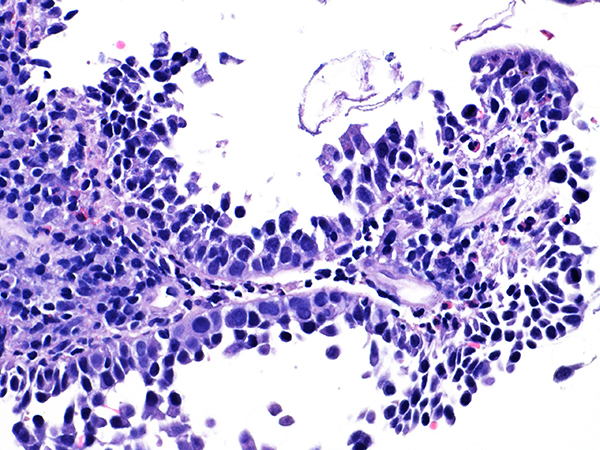

Area 1 - Soft Bx CIN 2 40x - High Power |

![]() Case 1